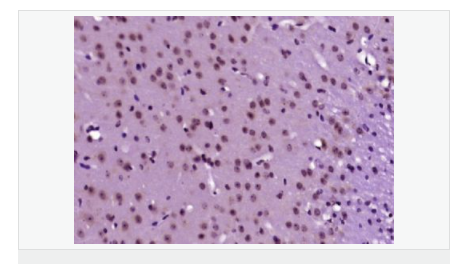

交叉反應(yīng):Human,Mouse,Rat(predicted:Dog,Pig,Cow,Rabbit,Sheep) 推薦應(yīng)用:WB,IHC-P,IHC-F,ICC,IF,ELISA

產(chǎn)品應(yīng)用WB=1:500-2000 ELISA=1:5000-10000 IHC-P=1:100-500 IHC-F=1:100-500 ICC=1:100-500 IF=1:100-500 (石蠟切片需做抗原修復(fù))

細(xì)胞定位細(xì)胞核 細(xì)胞漿